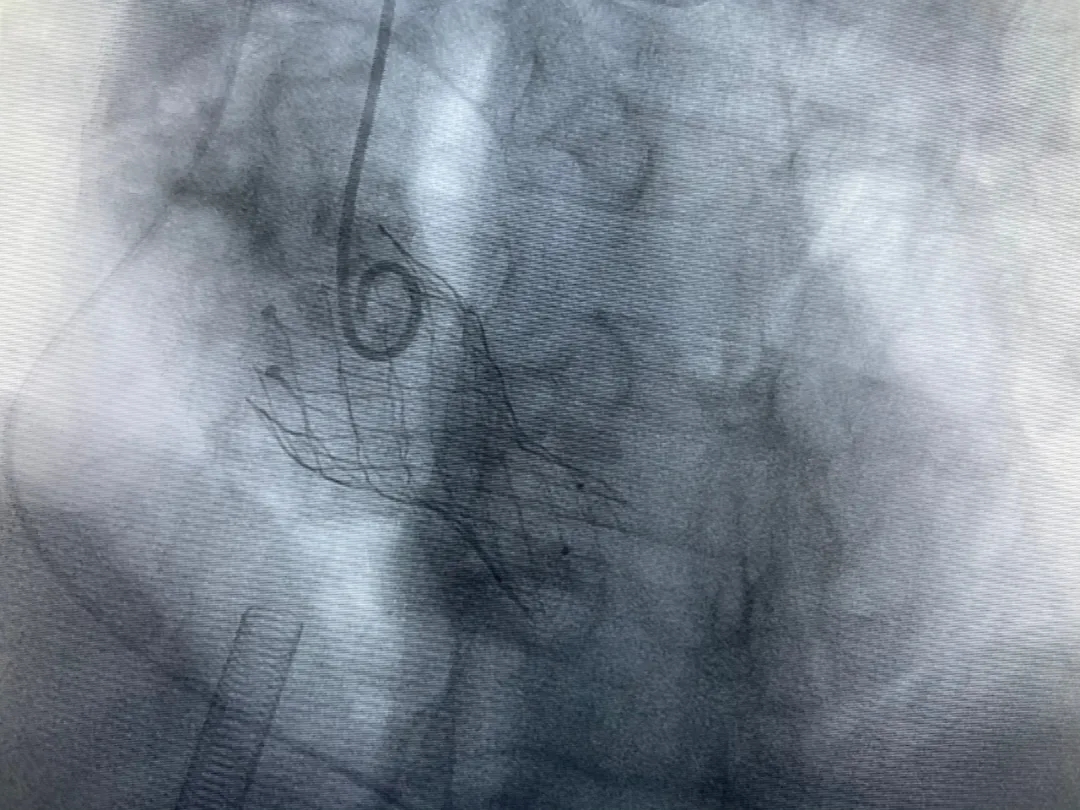

結(jié)合老人病情特點(diǎn):年齡高、室壁厚、左室腔小、瓣膜鈣化嚴(yán)重,術(shù)中球囊擴(kuò)張和瓣膜釋放過程有循環(huán)崩潰可能;為降低此種風(fēng)險、最大程度提高手術(shù)成功率,張金洲副院長在術(shù)前組織了由楊金保博士帶領(lǐng)的TAVR團(tuán)隊(duì)多次反復(fù)溝通、討論,制定了各種應(yīng)急處理方案。最終經(jīng)過TAVR團(tuán)隊(duì)的默契配合,手術(shù)歷時2小時,用20#球囊預(yù)擴(kuò)張后順利植入23#主動脈瓣生物瓣膜,再次后擴(kuò)后主動脈根部造影顯示:人工主動脈瓣生物瓣位置良好,瓣葉開閉正常;冠脈顯影良好。經(jīng)食道超聲顯示:主動脈瓣葉活動度良好,主動脈跨瓣壓差約35mmHg,未見瓣周漏及明顯返流。出手術(shù)室前老人便已蘇醒,自訴憋悶癥狀完全消失。